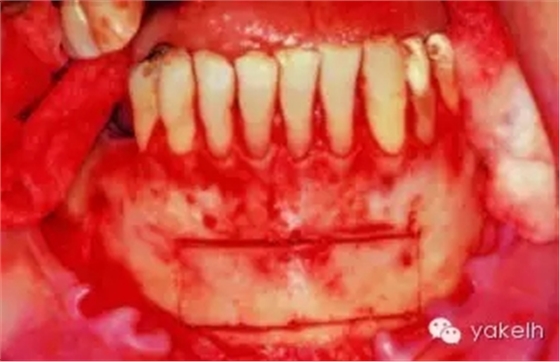

¤¤取骨入路容易是頦部供區(qū)的一個(gè)優(yōu)點(diǎn)。用含1∶100 000腎上腺素的2%利多卡因施行雙側(cè)下頜骨阻滯麻醉以及局部浸潤(rùn)麻醉,可采用齦溝內(nèi)切口或者前庭溝切口暴露頦部。在雙側(cè)下頜尖牙之間,距離膜齦聯(lián)合處1cm的黏膜上做前庭溝切口(圖13.16,圖13.17)。限制切口向遠(yuǎn)中延伸可以降低損傷頦神經(jīng)的風(fēng)險(xiǎn)。由于可以牽拉組織瓣,通過有限的切口也很容易到達(dá)頦部,前庭溝切口雖然很容易達(dá)頦部,但會(huì)造成更多的軟組織出血,還有可能形成口內(nèi)疤痕。當(dāng)有黏膜牙齦的缺損時(shí),不能采用齦溝內(nèi)入路,因?yàn)檫@可能導(dǎo)致牙齦的退縮。齦溝內(nèi)切口應(yīng)該延長(zhǎng)至雙側(cè)前磨牙區(qū)域(圖13.18)。翻起黏骨膜瓣,暴露雙側(cè)頦孔以及下頜骨下緣(頦點(diǎn)),在下頜骨的基底部,還需要額外的局部麻醉來阻滯頸神經(jīng)支配。

圖13.16 在雙側(cè)尖牙之間的黏膜上,做前庭溝切口。

圖13.17 通過前庭溝切口,翻起黏骨膜瓣,暴露下頜骨頦部。